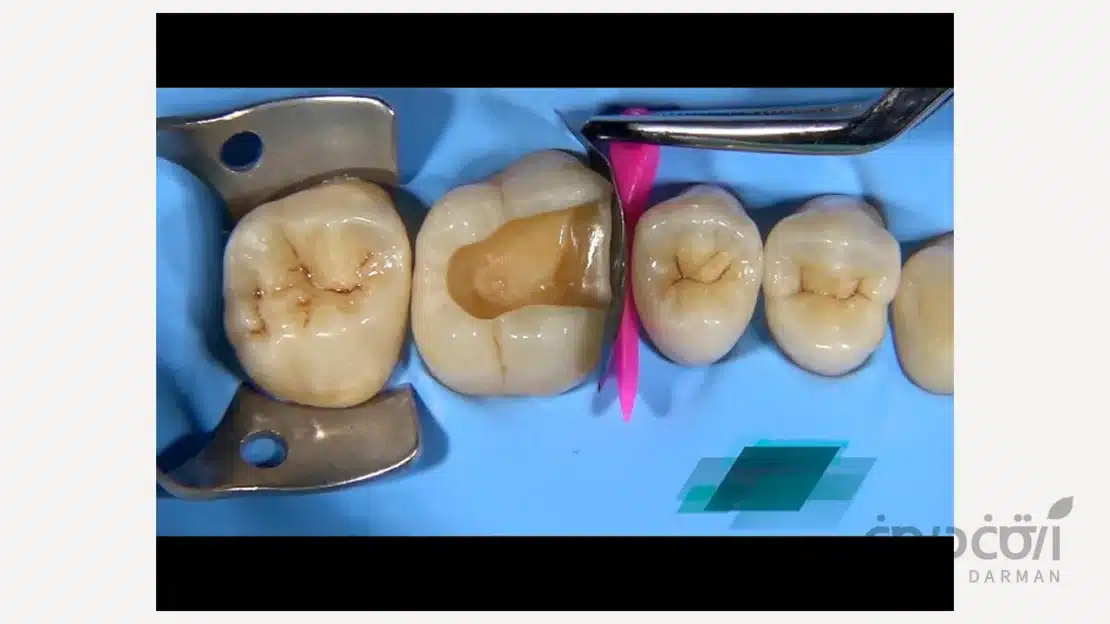

بیلداپ کامپوزیت، در واقع فرآیند بازسازی تاج دندان است. در این روش، دندانپزشک با استفاده از مواد کامپوزیتی پیشرفته و بهره گیری از تکنیک های لایه گذاری، آناتومی از دست رفته دندان را بازسازی می کند.

در این روش هدف تنها پر کردن یک حفره نیست؛ بلکه هدف، بازگرداندن فرم صحیح دندان، ایجاد نقاط تماس مناسب با دندان های مجاور و از همه مهم تر، بازگرداندن عملکرد دندان برای جویدن است. در بیلداپ، مواد ترمیمی با استفاده از سیستمهای باندینگ پیشرفته به بافت دندان متصل می شوند و یک ساختار یکپارچه را ایجاد می کنند که می تواند نیروهای وارده را به صورت متعادل در طول ریشه پخش کند.

کامپوزیت های نوین حاوی ذرات نانوسرامیکی هستند که مقاومت فشاری و سایشی آن ها بسیار نزدیک به دندان طبیعی است. زمانی که این مواد با پروتکل های صحیح باندینگ (چسباندن) به دندان متصل می شوند، عملا با دندان یکی شده و دندان را از درون تقویت می کنند.

- کنترل فشارهای مخرب: تنظیم دقیق ارتفاع دندان (اکلوژن) بسیار حیاتی است. اگر دندان بازسازی شده زودتر از سایر دندان ها با فک مقابل برخورد کند، احتمال شکستن آن بالاست.